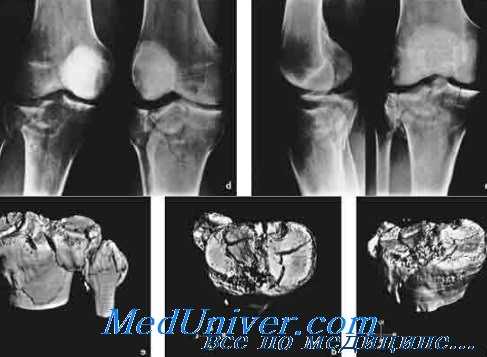

Компьютерная томография в диагностике опухолей конечностей

Компьютерная томография оказалась чрезвычайно эффективной в диагностике новообразований костей и мягких тканей конечностей. Как правило, врач неотложной помощи направляет больных с подозрением на опухоль кости к специалисту, но возрастающая доступность КТ может сделать ее частью рутинного первичного обследования.

Хотя КТ не всегда достаточна для постановки диагноза, часто она дает важную информацию о плотности объемного образования, его отношений к нормальной кости, нервам и сосудам, а также о наличии или отсутствии рецидива у оперированных больных. Как указывалось выше, при первичном выявлении новообразований конечностей радиоизотопное сканирование является более чувствительным инструментом. Возможно, КТ более информативна при планировании биопсии и специфической терапии.